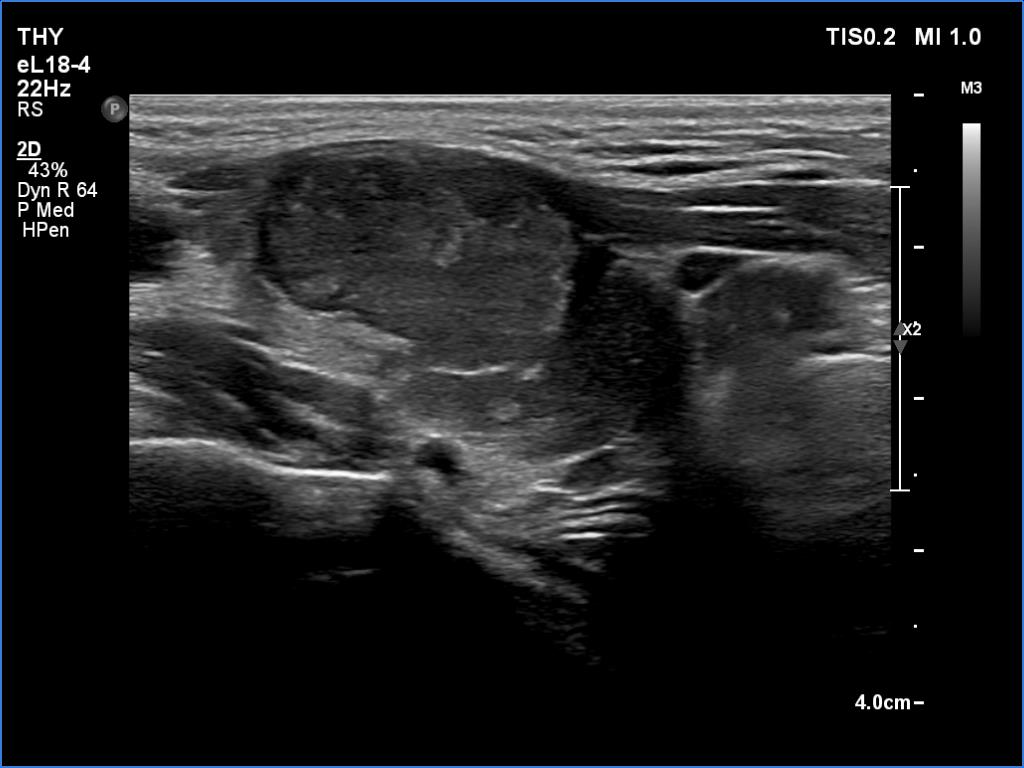

Lateral part of the right lobe, longitudinal scan. This nodule has irregular borders.